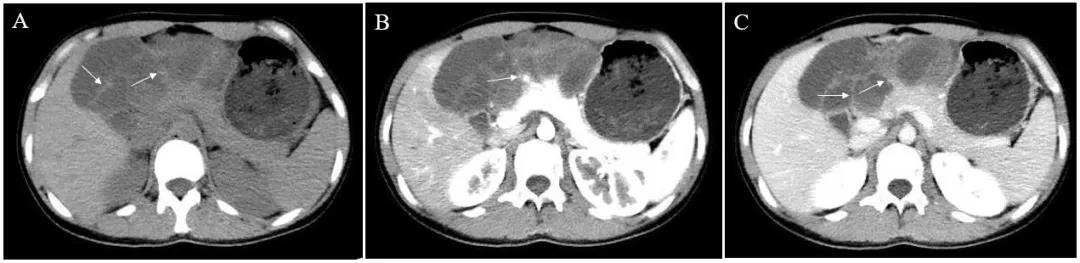

我院 CT 和 MRI 考虑胰腺囊腺瘤可能性大。(图 1)

图 1. 腹部增强 CT 显示胰颈体部囊实性占位,内有分隔 (A),分隔在增强期可见强化 (B 和 C)。

影像学表现为囊实性占位,囊腔大小不一,囊腔间有分隔,增强时分隔可见强化;